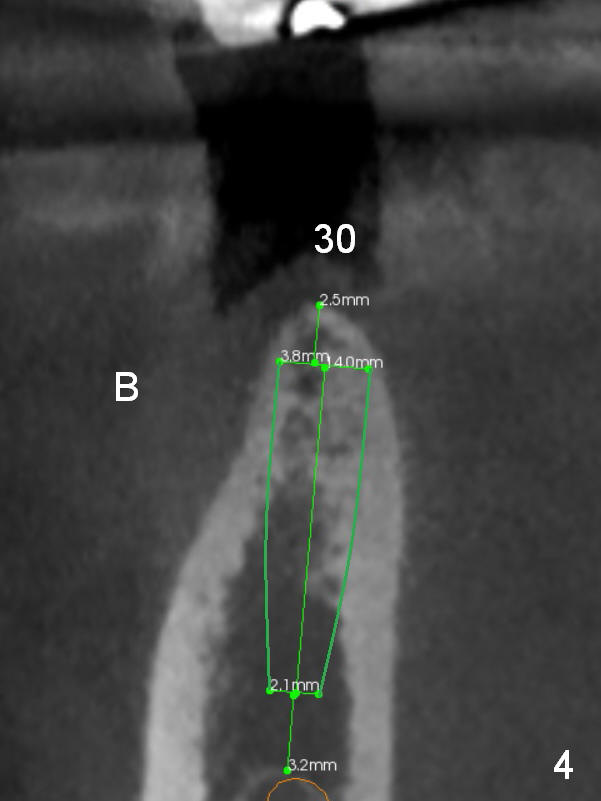

A 47-year-old woman has had 3 bridges. One of them (the lower right) is broken down. The patient requests removing the tooth #31 (Fig.1 CBCT), because of difficulty in keeping it clean. Since the buccal plate is thin (Fig.2 (axial section), 3 (coronal section) >) or absent (Fig.2 *), a 5 mm implant will be placed lingually (Clindamycin). Tap will be used prior to implant placement.